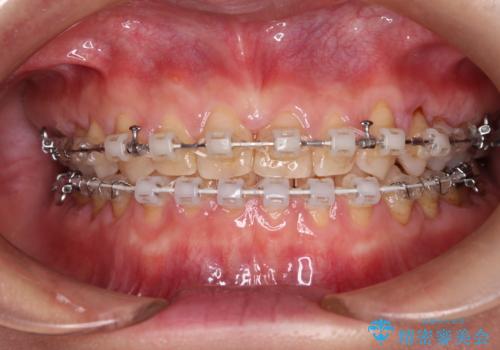

【審美装置】すきっ歯をワイヤー装置で治したい

- 前歯のすきっ歯が気になるということで来院されました。今回は抜歯はしないためワイヤー矯正かインビザライン矯正のどちらでも治療可能でしたが、患者さまのご希望により表のワイヤー装置にて治療をおこないました。

前歯に隙間がいくつかあったため、今回は上下でゴムかけを行いスペースを埋めるための力をかけて閉じました。もう少し早く終了する予定でしたが、ブラッシング不良による歯肉腫脹があり、一部スペースクローズに時間がかかりました。